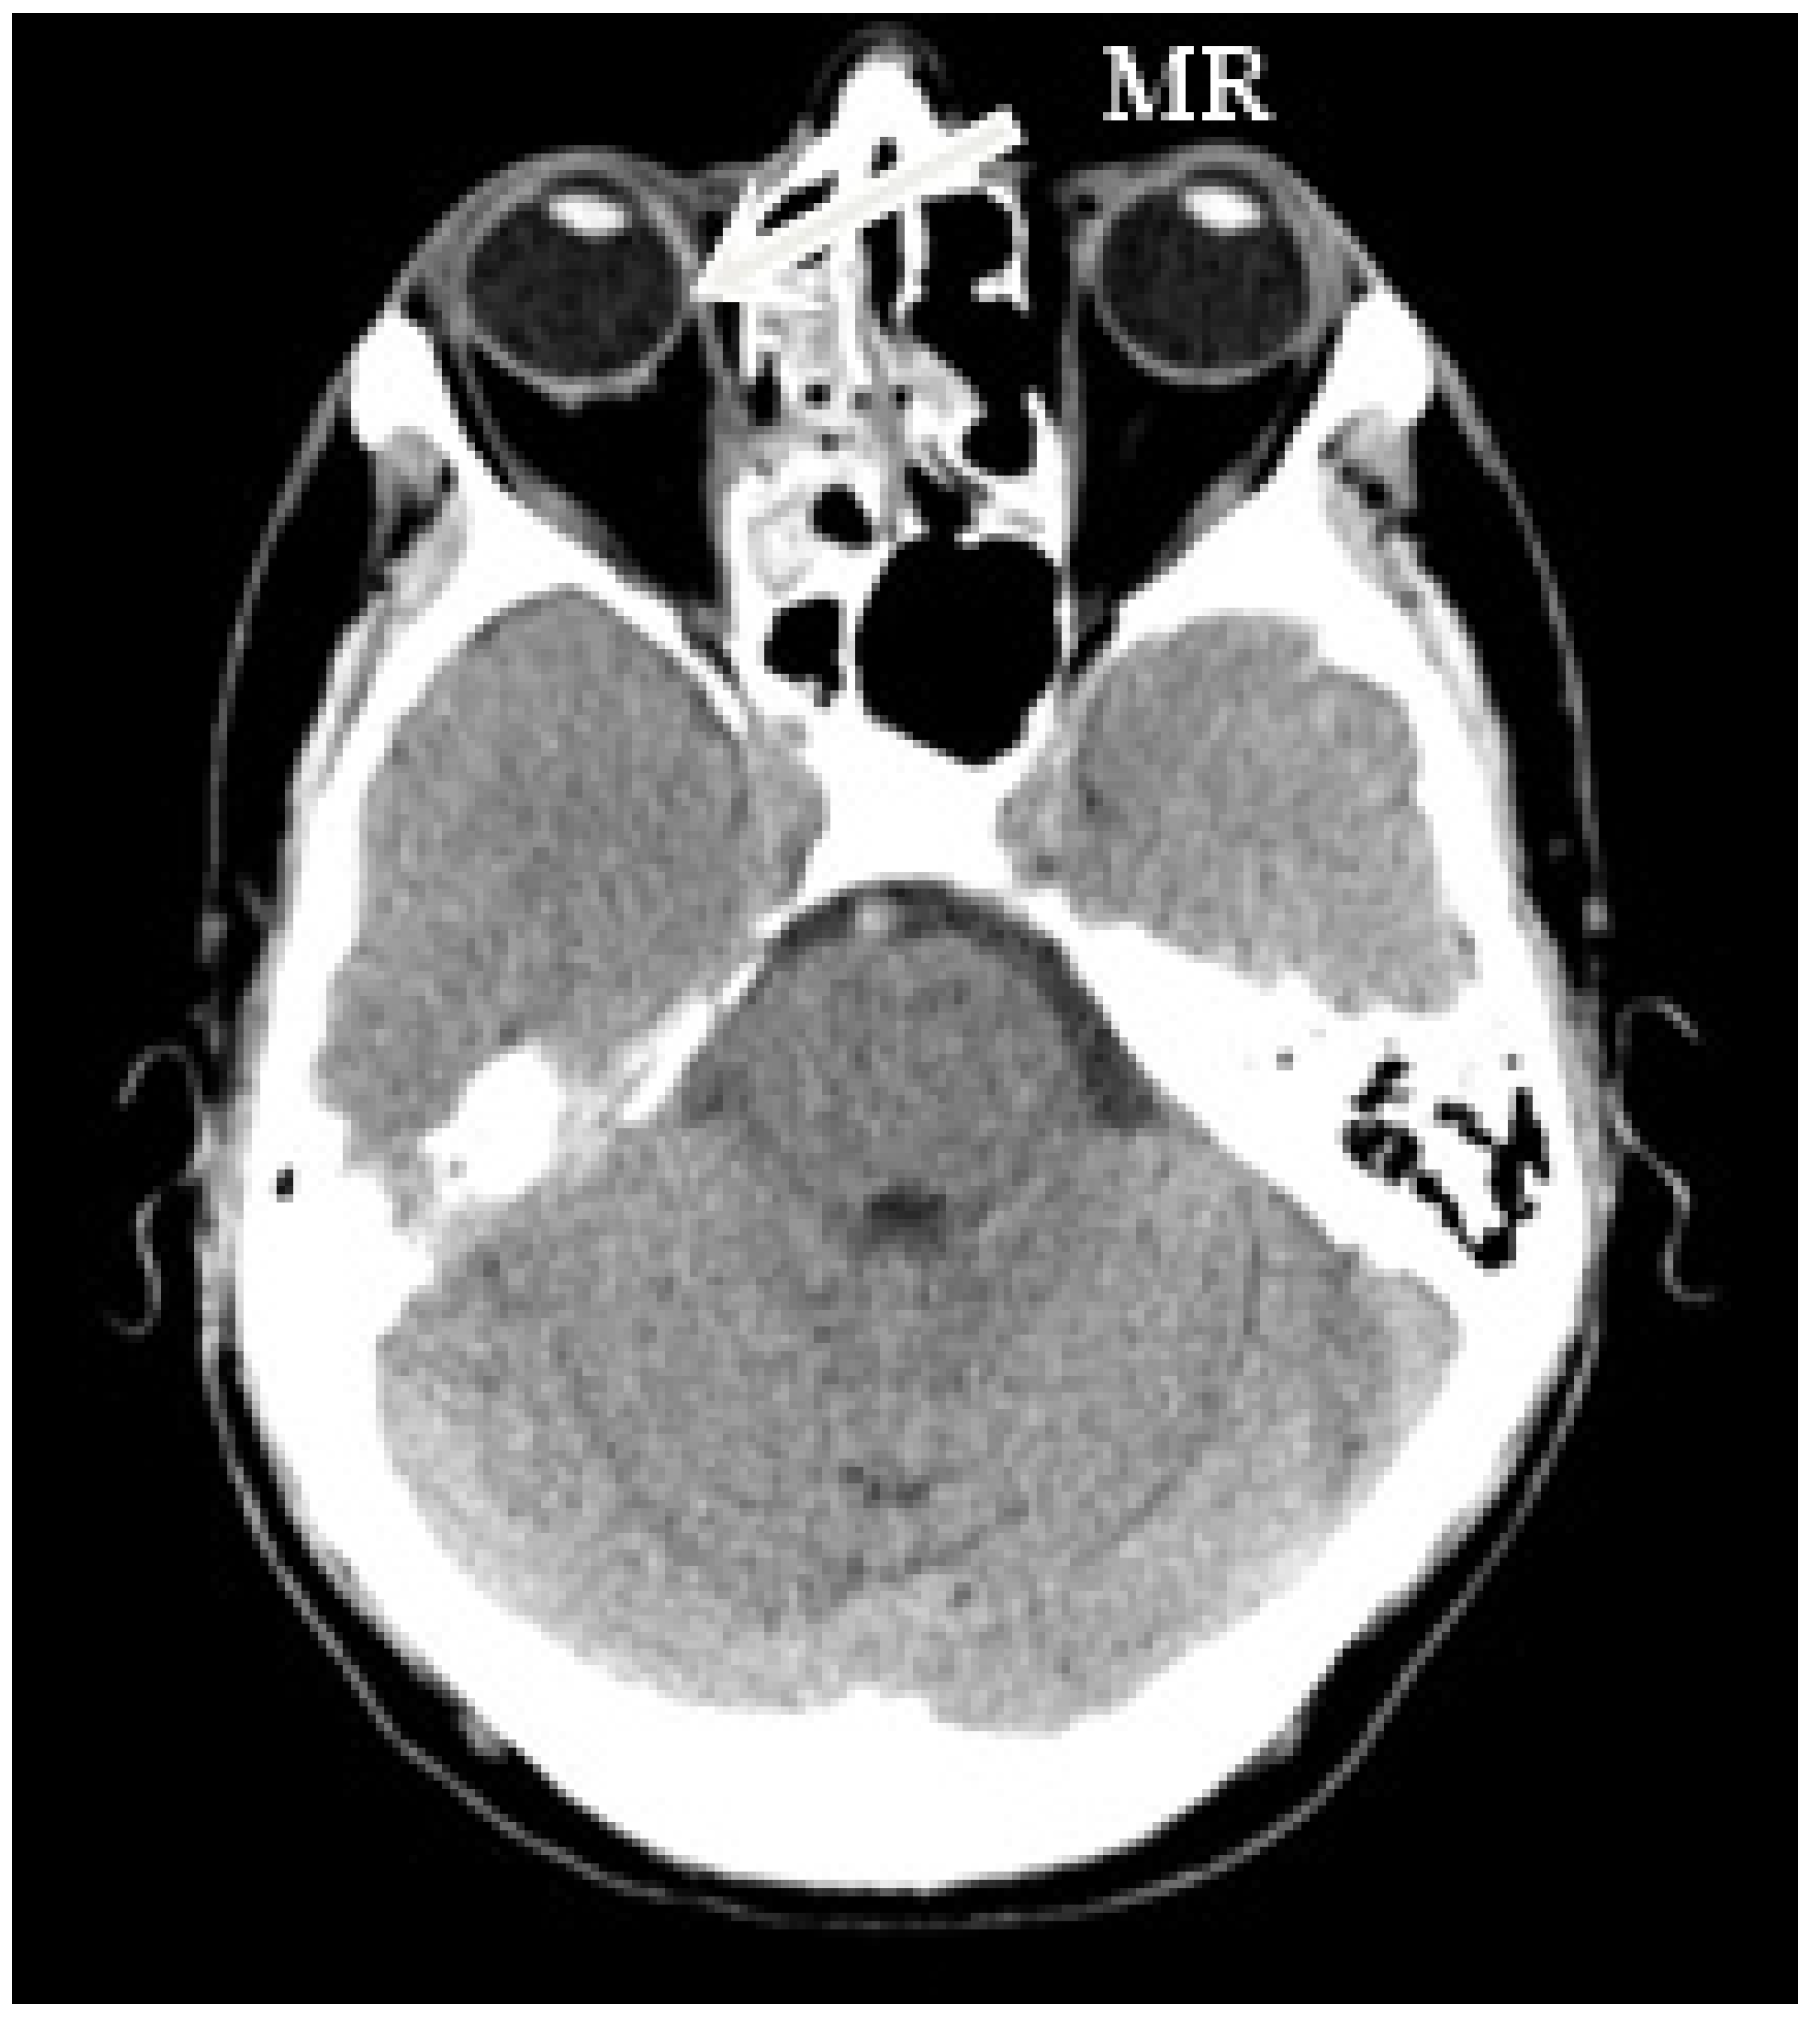

The right side was more commonly affected (five right, two left) (Figure 1). The medial orbital wall was fractured in all but one case (case 5) where the damage involved the inferior wall. Prolapse of the orbital fat and soft tissue into the field of injury were described in all patients who experienced medial wall defect. Air-filled cavities were commonly seen around the injury and the characteristic lesions for conducted endoscopic surgery were visible on all scans (Figure 2).

Figure 2. Postoperative coronal MRI scan showing bilateral ethmoidectomy, antrostomy, and uncinectomy in chronic maxillary sinusitis with significant mucosal thickening. MRI scan demonstrates the right medial rectus displacement.